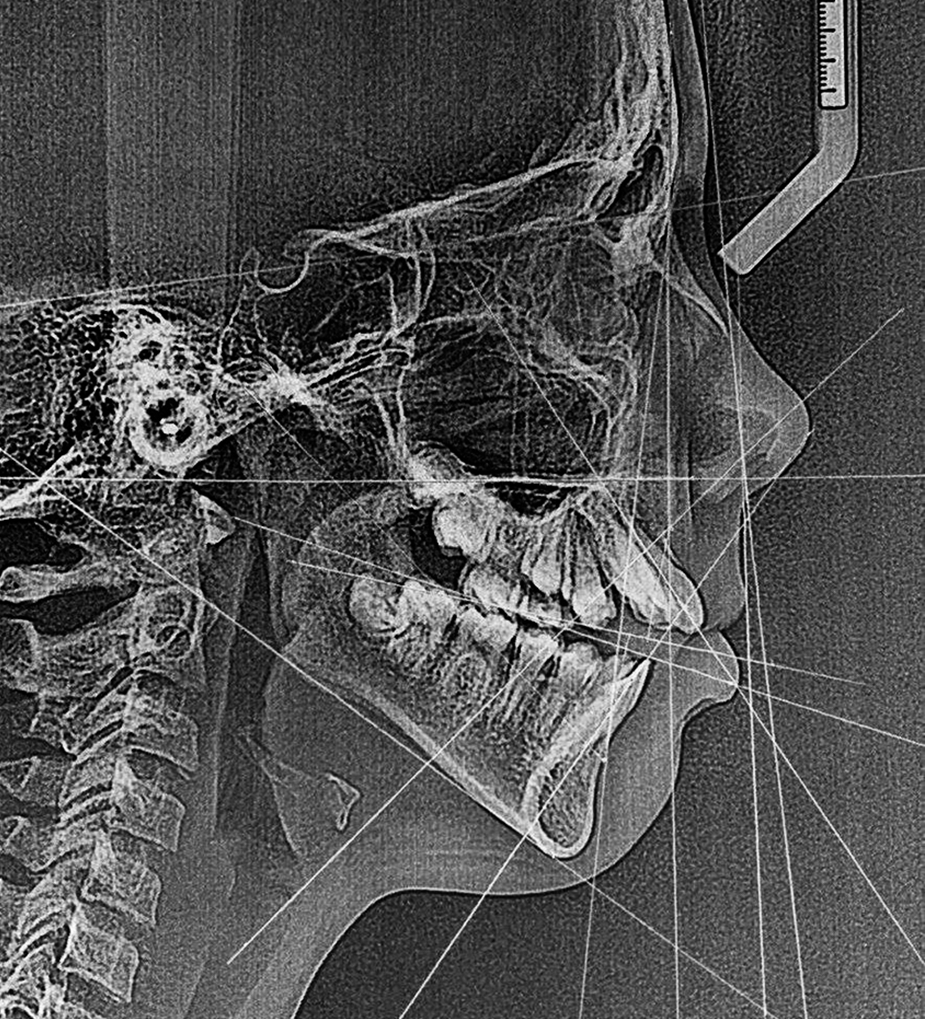

Проведённая челюстно-лицевая операция по природным и уникальным ориентирам человека - Шесть Элементов. Произошло восстановление костных структур черепа, увеличение объёма воздухоносных путей, ВНЧС в уникальной центрике, достигнута природная окклюзия.